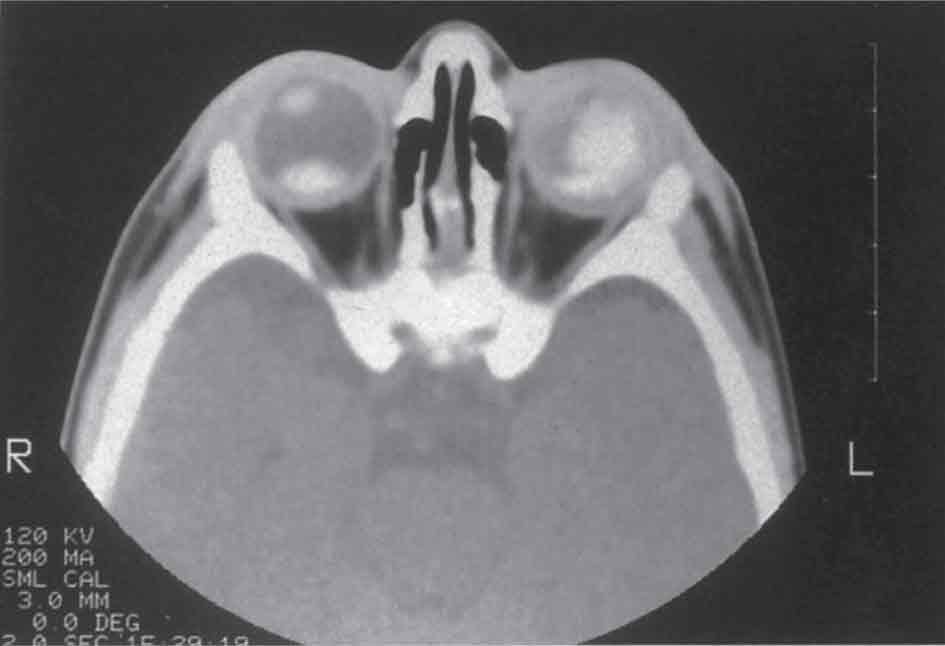

الشكل (2): التصوير بالأمواج الصوتية للورم الميلانيني المشيمي الخبيث بالشكل الفطر.

-(5 التصوير بالأمواج فوق الصوتية: يفيد في تقدير أبعاد الورم وامتداده إلى خارج كرة العين، كما يفيد في التوجه لتحديد نوعية الورم من خلال إظهاره كثافة الورم، ويعد وجود التقعر المشيمي والظل القاتم في الحجاج خلف الورم من العلامات المميزة للميلانوم المشيمي بالشكل القبة، كما يعد الشكل الفطري للكتلة مميزاً لهذا الورم حين وجوده (الشكل 2). ويستخدم تخطيط الصدى العيني بهدف التشخيص، ولاسيما حين وجود كثافة في الأوساط الشفافة؛ وبهدف المراقبة الدورية.